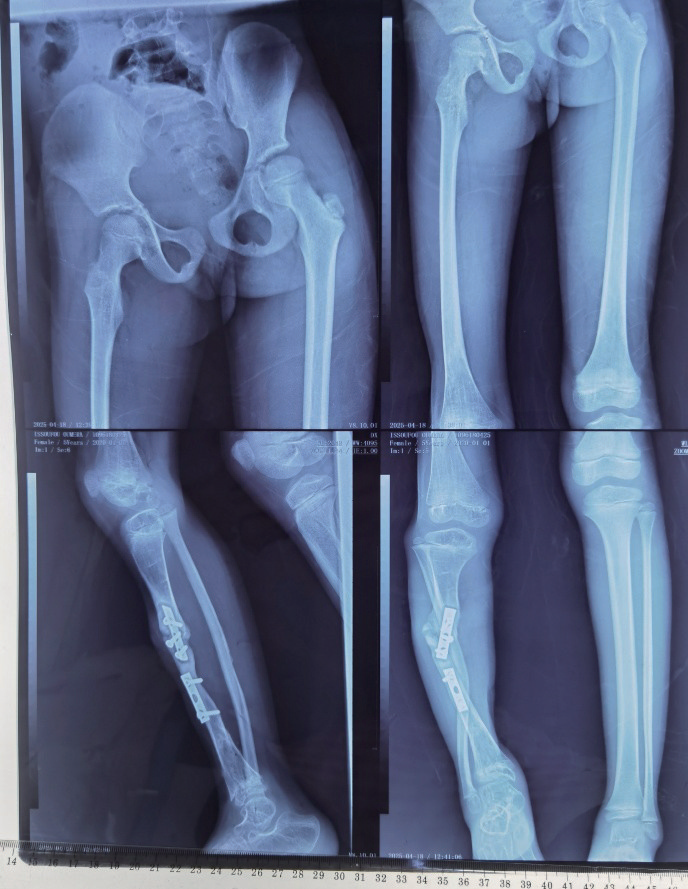

术前评估显示,患儿右小腿明显短缩,皮肤可见多处陈旧手术瘢痕,踝关节呈30°固定内翻,足部力线严重异常,无法负重(图5)。X线片提示右胫骨中段骨不连、断端硬化萎缩、内固定松动,腓骨代偿性增粗弯曲,踝关节面倾斜,符合创伤后骨缺损合并继发性踝关节畸形的典型表现,最终诊断为右胫骨创伤后大段骨缺损伴踝关节固定性内翻畸形(图6)。

image.png

图5 术前患肢明显缩短畸形

图6 术前X线片

术后管理是确保手术成效的关键环节。手术团队在术后第7天启动骨搬运程序,以每日1 mm的速度分4次调节螺纹杆,推动近、远端骨块向缺损中心同步靠拢(图7)。每周通过X线监测骨再生进展及对合端对位情况,待原3.5 cm骨缺损闭合后,继续延长4.0 cm,直至双下肢恢复等长。针道护理严格执行每日酒精消毒,有效预防感染。康复方面,术后第2天即指导患儿进行股四头肌等长收缩及膝、踝关节主动活动,并鼓励拄拐部分负重行走,以促进局部血运与骨再生。整个过程密切防范轴偏、关节挛缩等并发症,及时调整外固定支架,保障搬运过程顺利。术后6个月影像学评估显示,骨缺损已完全修复,再生骨矿化良好,踝关节力线恢复正常,双下肢长度一致。功能上,患儿可实现独立行走,步态基本对称,踝关节稳定且无疼痛,实现了结构与功能的双重康复。

图7 骨搬运治疗后X线片